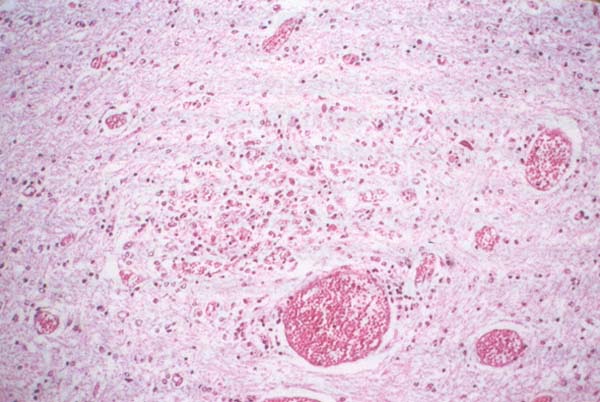

- Mikroskopi, nöronların sitoplazmasında büyük vakuollerin varlığını ortaya koyar; bu bir tanı lezyonu olarak kabul edilir.

- Beyin kanaması, ödem ve ventriküler genişleme (Şekil 176)

- Beyin iltihabı (Şekil 177)

Şekil 176 : Toksoplazmoz. Beyin kanaması, ödem ve ventriküler dilatasyon. Örnek %10 formalin solüsyonunda fiksasyona tabi tutuldu.

Şekil 177 : Toksoplazmoz. Beyin iltihabı (ensefalit). Takizoitler, kistleşip bradizoitler ürettikleri beyin boyunca dağılırlar.